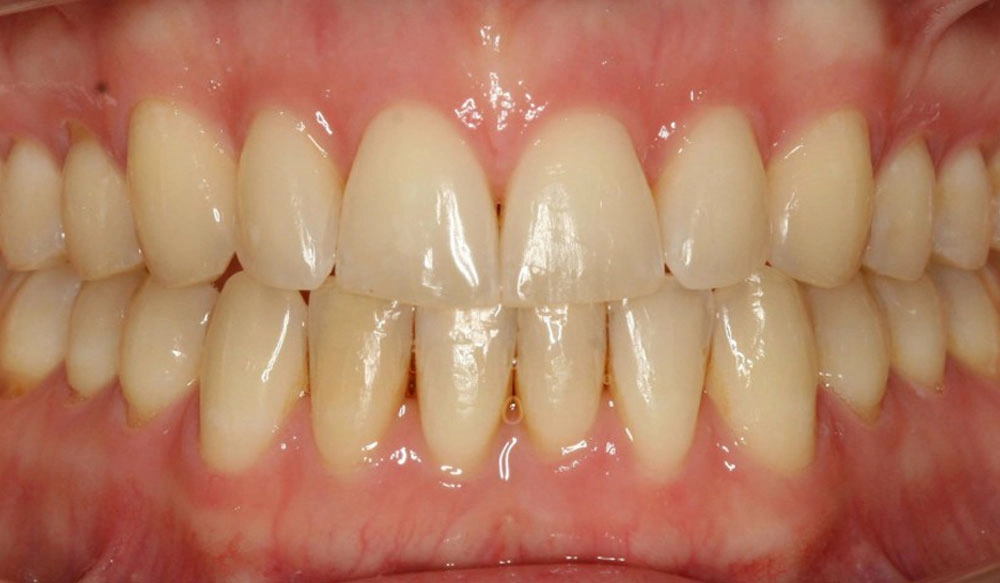

Crowding

Crowding is the condition in which there is a discrepancy between tooth size and space available for the teeth to be aligned in the dental arch

Patient Information:

Age: 17

Gender: female

Invisalign Treatment Option: Invisalign Comprehensive

Total Treatment Time:

29 months